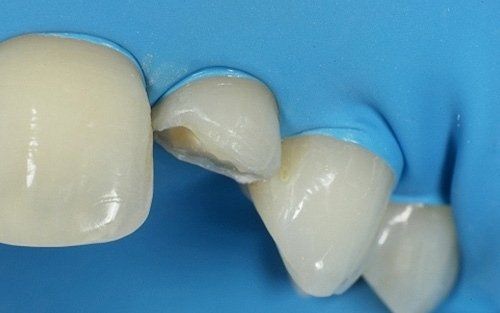

Qui raffigurato l'incisivo laterale di destra, dopo la rimozione del vecchio restauro.

Il restauro definitivo sul dente laterale: notare la buona integrazione fra il dente e il restauro.